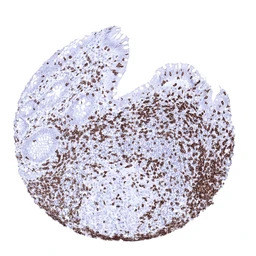

IHC-P analysis of human diffuse large B-cell lymphoma tissue section using GTX04389 CD3 epsilon antibody [MSVA-003R] HistoMAX.

Diffuse large B cell lymphoma infiltrated by numerous CD3 epsilon positive non neoplastic lymphocytes.